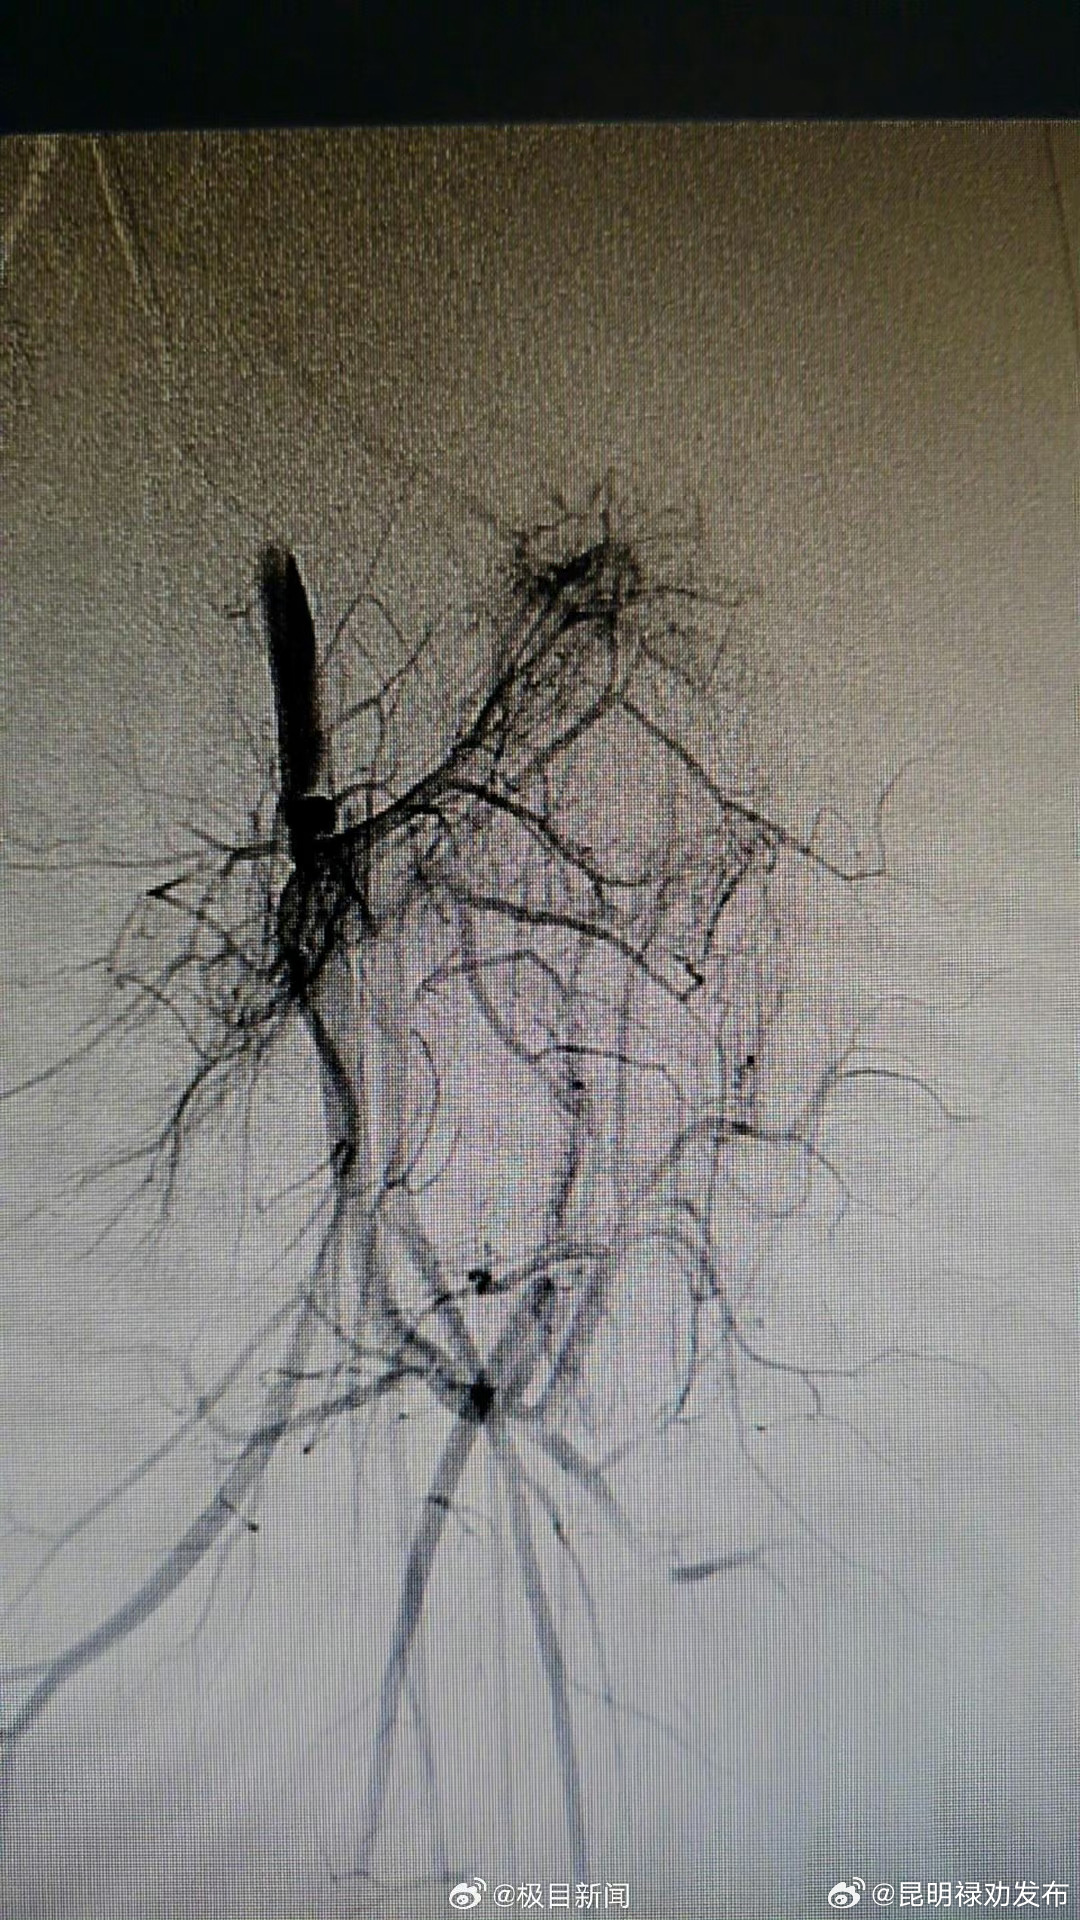

7岁女童可可(化名)出生时臀部和左腿有一大片红斑,家长以为是“胎记”。随着可可长大,家长意外发现“胎记”摸上去有些烫手,局部还能触及到搏动感,孩子的双腿长短、粗细不同,走路时一瘸一拐。辗转多家医院后,可可在武汉儿童医院被确诊患血管罕见病——P-W综合征,腿部血管有多发畸形,经微创介入手术,医生用头发丝细的导管封堵住杂乱无章的血管,可可病情明显好转。8月6日,可可在武汉儿童医院介入放射科/血管瘤科完成了最后一期手术,几天后将出院回家休养。